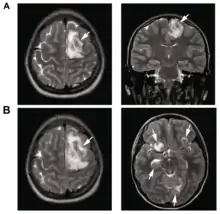

.png.webp)

B: T1-weighted MRI showing expansion of the brain lesions 4 days later